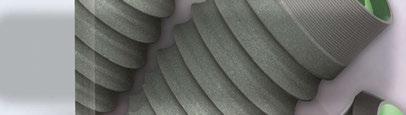

The basic macro structure of modern dental implant has not changed much since its inception. The implant that Brånemark first placed in his patients in 1965 when the original Brånemark implant was created was cylindrical; later on tapered forms appeared.1 We have seen the use of different thread designs with the top three today being V-threads, square threads, and reverse buttress styles. To address the ever-present issue of crestal bone loss, implants have evolved by moving the connection from an external position to internal, moving the platform emergence from the outside of the implant circumference to inside it by platform switching. A host of collar designs – smooth, polished, machined, micro-threaded, tissue level, and bone level have all been utilized. All this being said, the macro structure of these implants all function as a compression, friction-fit screw in the osteotomy to achieve primary stability at placement. This type of compression stability results in detrimental short-term sequalae that are not overcome until osseointegration is completed.

With its origins in heavy industry, a unique thread design is able to achieve the union of two pieces of metal without any damage to each piece. In a nutshell, it has the ability to “stitch” two pieces into one with an incredibly strong union. In 2015, Osteocentric Technologies (Austin, TX) was founded, and the concept of Unifi MI was born. This unique and revolutionary thread design was first utilized for fixation devices in orthopedics. Following the success in that field, the patented thread

How Unifi MI is different

Unifi MI stands for Unifi Mechanical Integration. The Unifi threads interlock a flank of bone between them and not only reduces the movement of the implant (Figure 3), but also distributes forces in a very different way than traditional threads or implants. Let me make this clear; this is not a replacement for the development of osseointegration or secondary implant healing. This is a way to achieve outstanding primary stability, resistance to micro-motion, and better stress distribution in the peri-implant bone not only at the early phases of treatment, but also for the entire life of the implant in function.

The configuration of the implant progressed through a series of macro configurations starting with a design very close to the design used in orthopedics. The implant developed over time through testing to the current design (Figure 5). The prototype implants are in the following sizes: 3.7 mm, 4.2 mm, and 5.5

mm diameters with lengths ranging from 8 mm-12 mm in length (Figure 6). Likely by the time this article is published, FDA clearance will be completed.